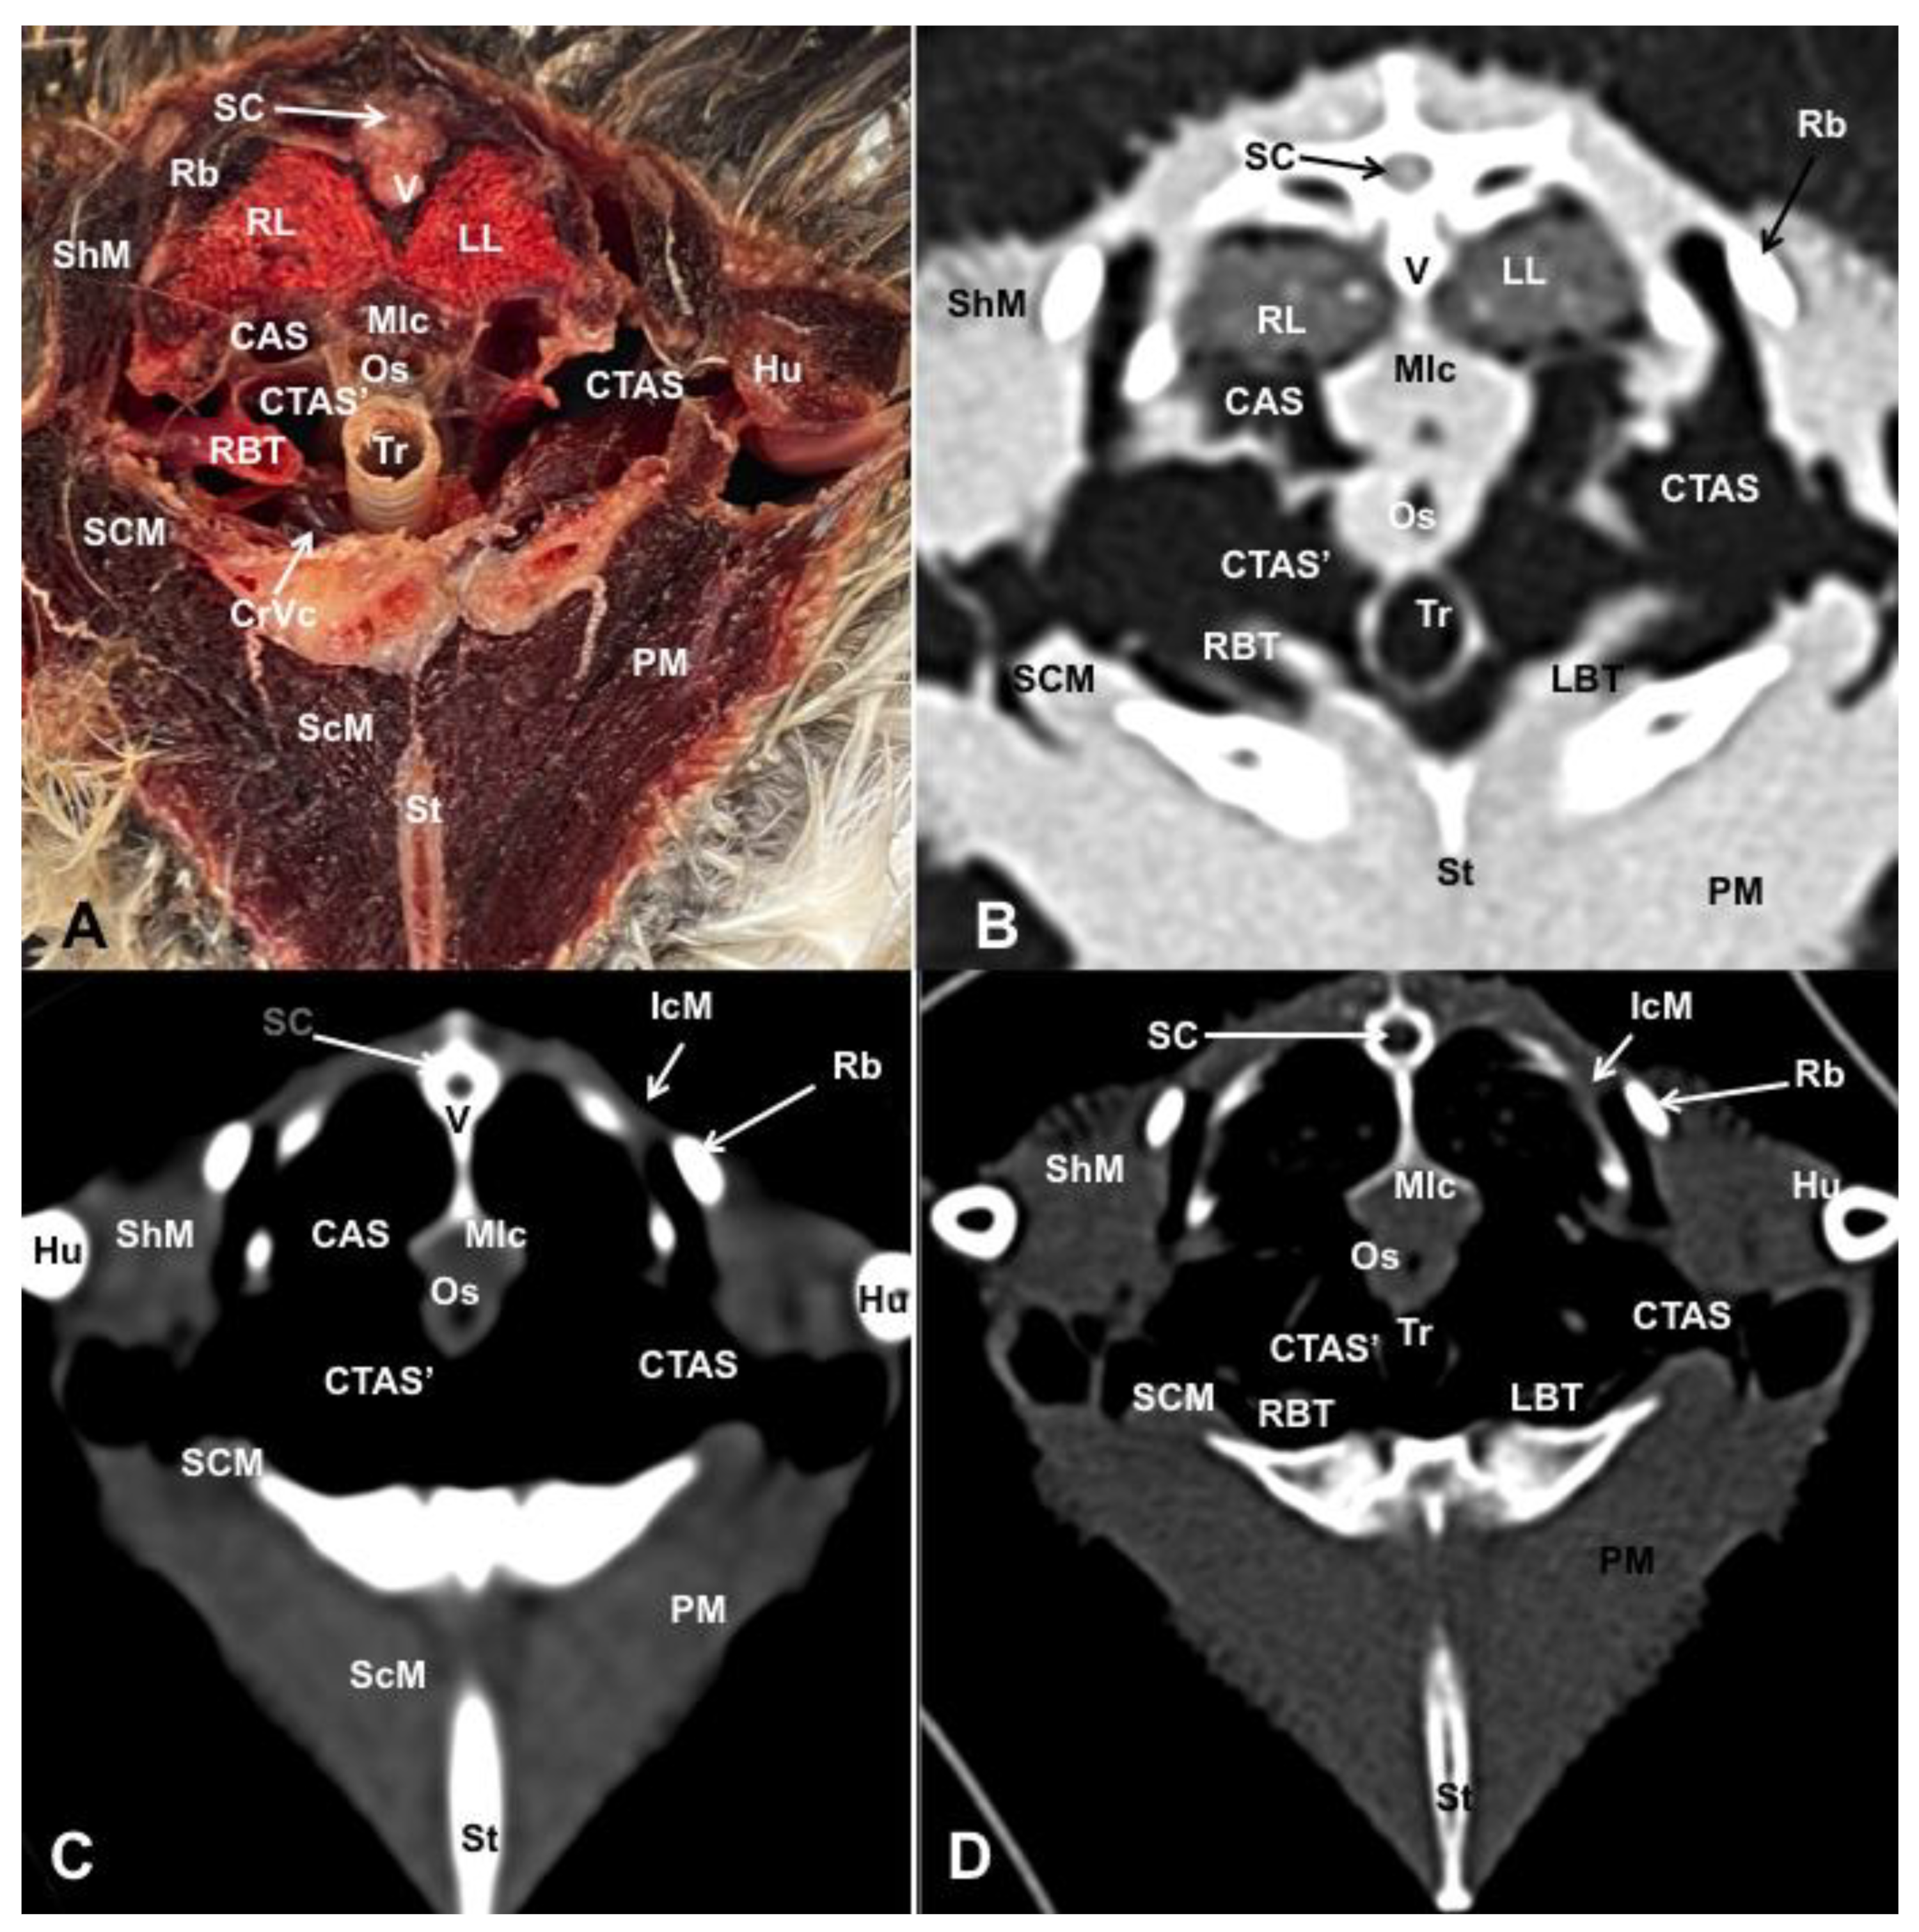

3.1. Anatomical Dissections and Cross-Sections

3.2. Computed Tomography Images